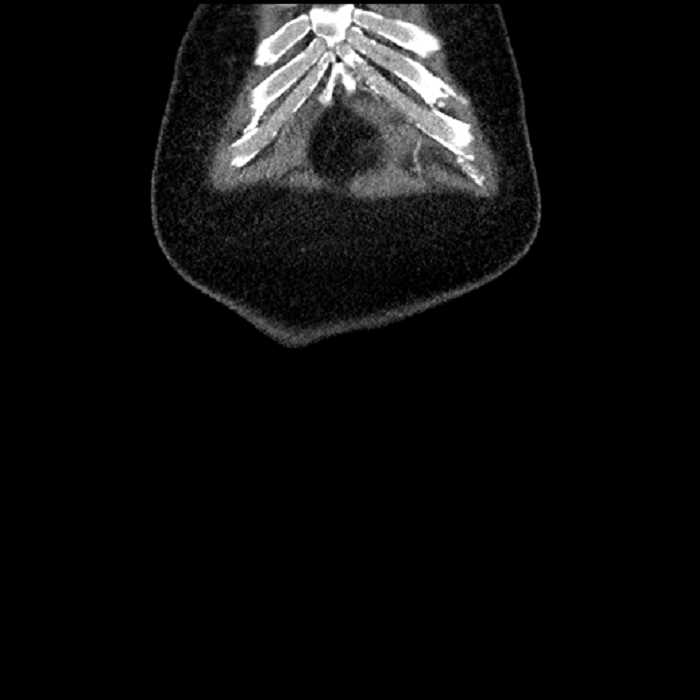

Age: 63

Sex: Male

Indication: Abdominal pain

• Large fluid density structure in hepatic segments 7 and 8 measuring 10 x 7 x 7 cm with internal septation and circumferential ill-defined low density compatible with edema

• Peripherally enhancing subcapsular collections along the anterior margin of the left hepatic lobe measuring 3 x 1 cm and 2 x 1 cm

• Hepatic abscess

Acute sigmoid diverticulitis complicated by a small contained perforation and a large abscess in the right hepatic lobe. Additional small subcapsular abscesses along the anterior margin of the left hepatic lobe.

• The classic CT imaging appearance is a double target sign with internal low density surrounded by an internal enhancing rim (capsule) and a low density external rim (edema)

Hepatic abscess showing the double target sign with low density internally surrounded by a thin inner enhancing rim (red arrow) and ill-defined outer low density rim (yellow arrow). Blue arrow indicates an internal septation. Red arrows: additional smaller subcapsular abscesses. Red arrow: focal contained perforation associated with diverticulitis.